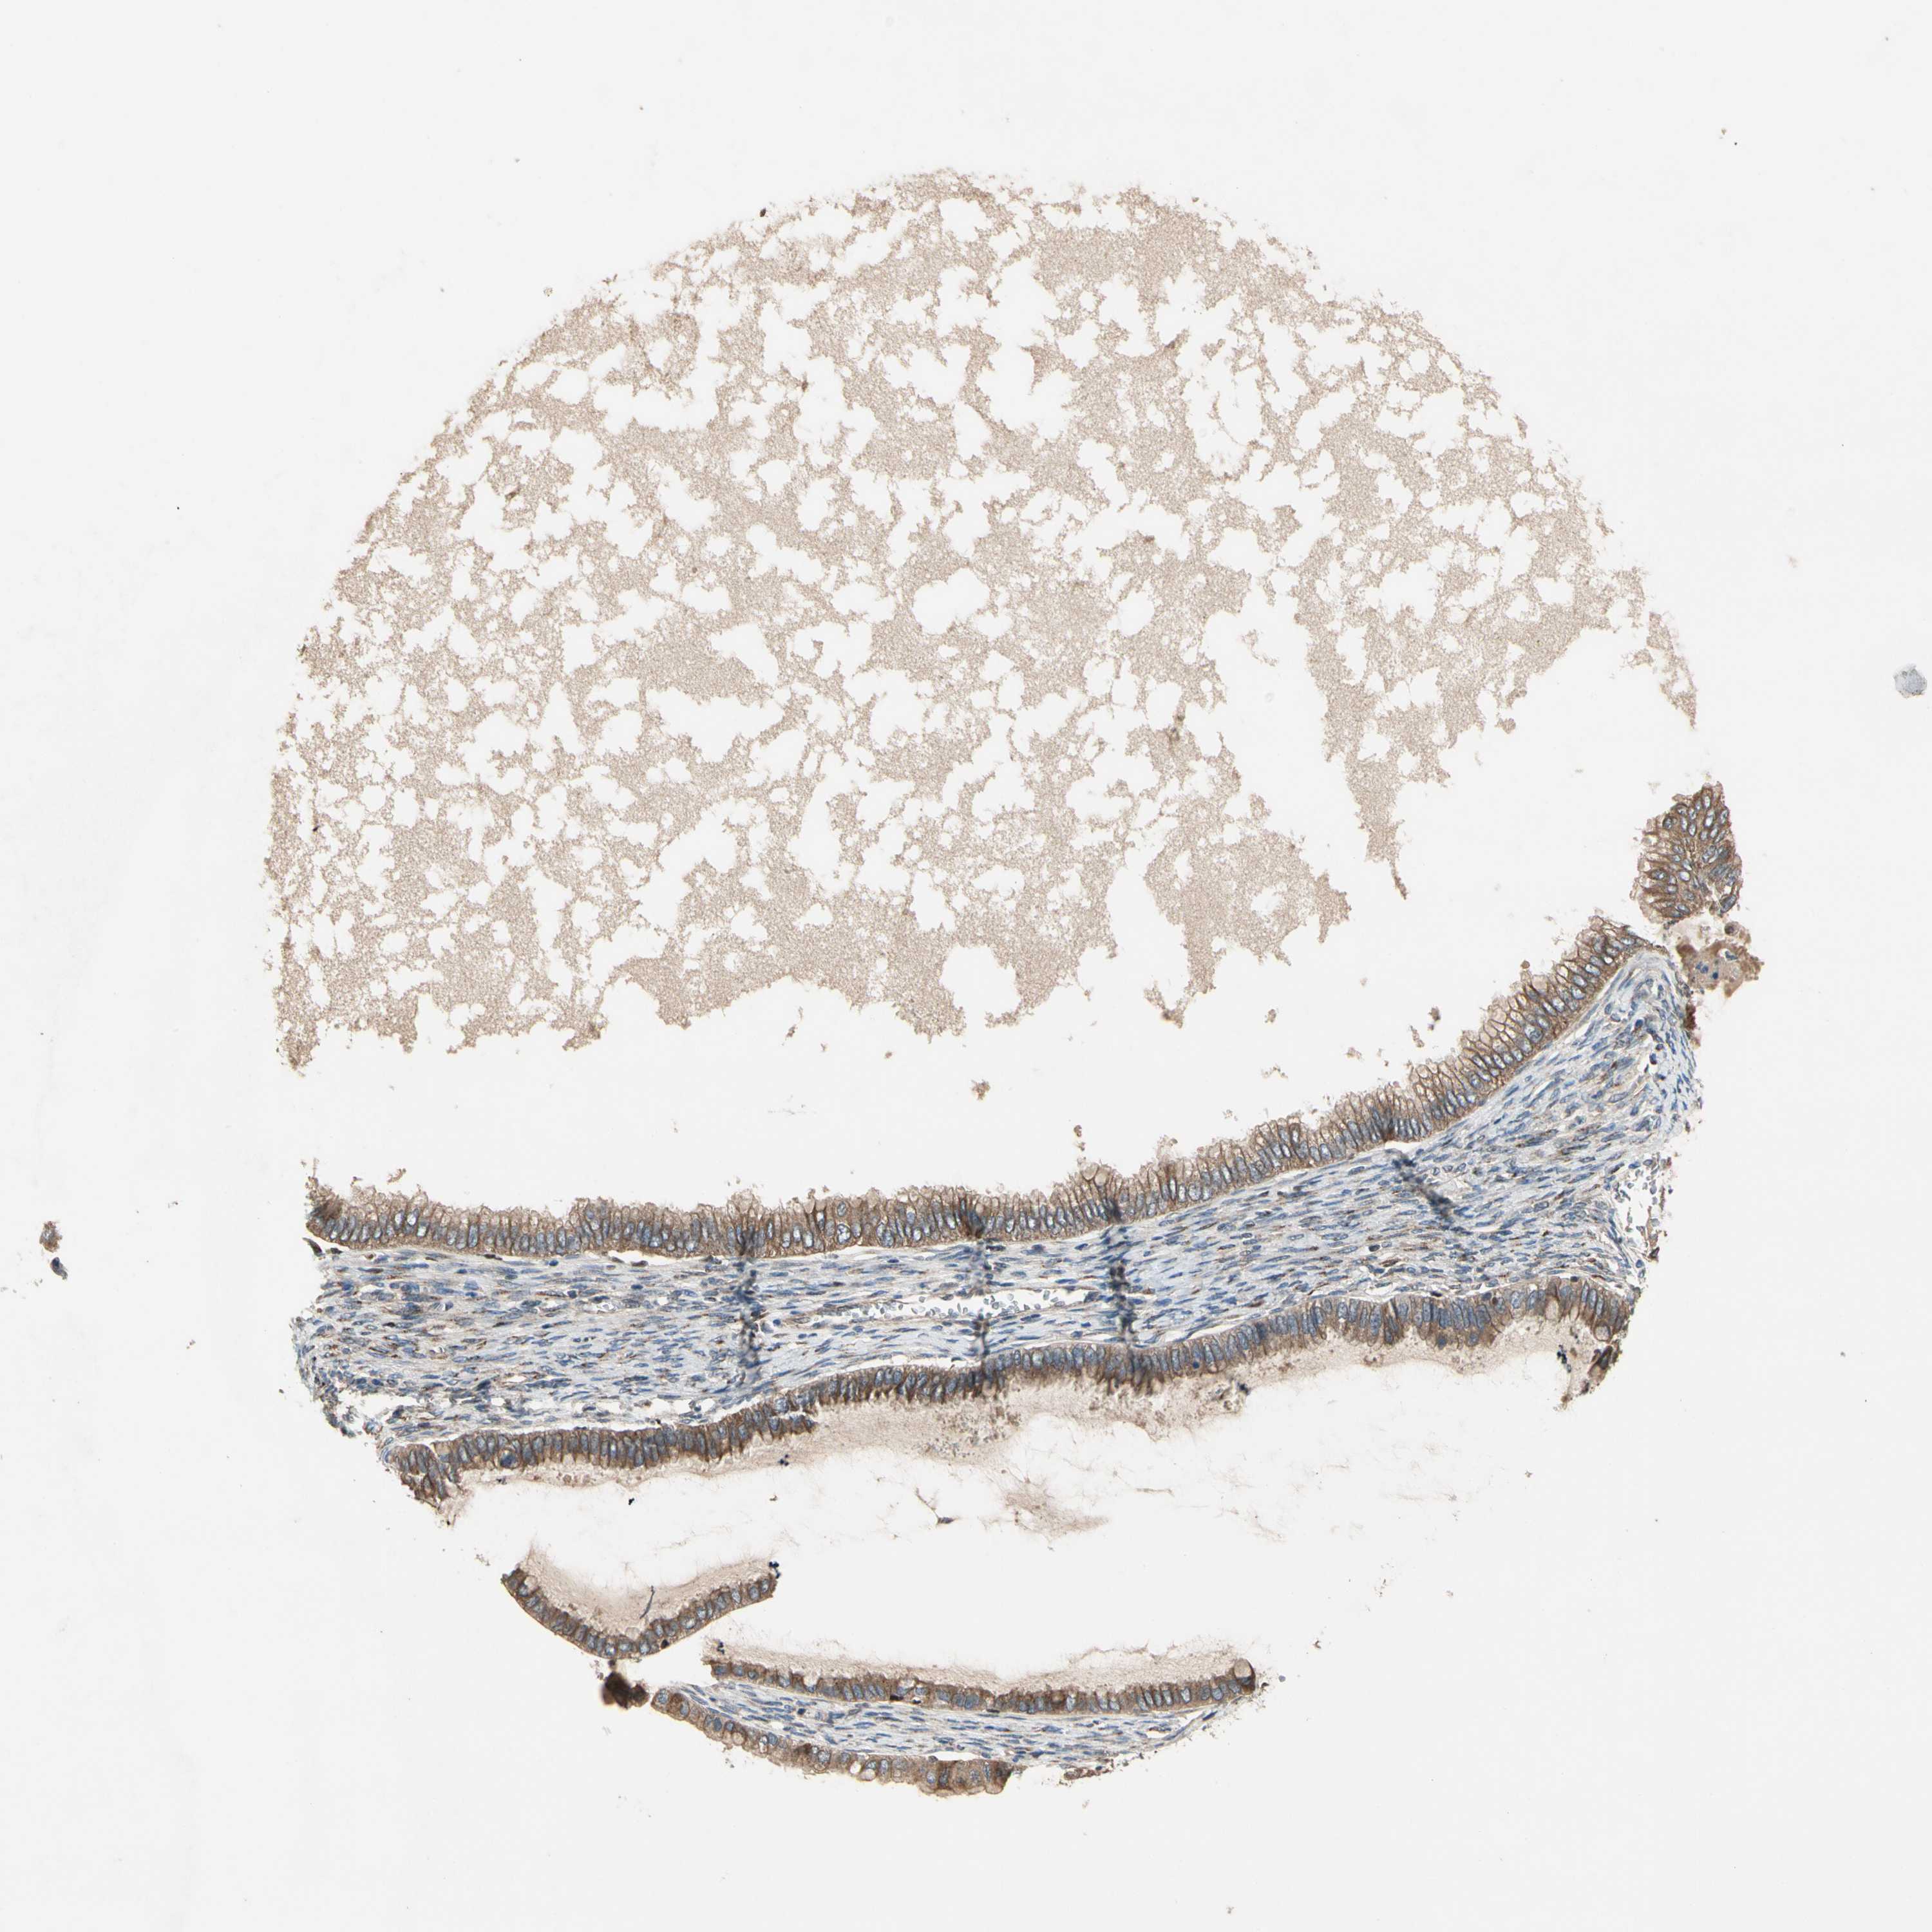

OVARIAN CANCER - Protein expressioni

A mouse-over function shows sample information and annotation data. Click on an image to view it in a full screen mode. Samples can be filtered based on level of antibody staining by selecting one or several of the following categories: high, medium, low and not detected. The assay and annotation is described here.

Note that samples used for immunohistochemistry by the Human Protein Atlas do not correspond to samples in the TCGA dataset.

Antibody stainingi

Antibody staining in the annotated cell types in the current human tissue is reported as not detected, low, medium, or high, based on conventional immunohistochemistry profiling in selected tissues. This score is based on the combination of the staining intensity and fraction of stained cells.

Each image is clickable and will lead to virtual microscopy that enables deeper exploration of all samples and also displays staining intensity scores, fraction scores and subcellular localization as well as patient and tissue information for each sample.

Antibody HPA008241

Staining

High

Medium

Low

Not detected

Intensity

Strong

Moderate

Weak

Negative

Quantity

>75%

75%-25%

<25%

None

Location

Nuclear

Cytoplasmic/membranous

Cytoplasmic/membranous,nuclear

Cystadenocarcinoma, serous, NOS

Carcinoma, endometroid

Cystadenocarcinoma, mucinous, NOS

Carcinoma, NOS